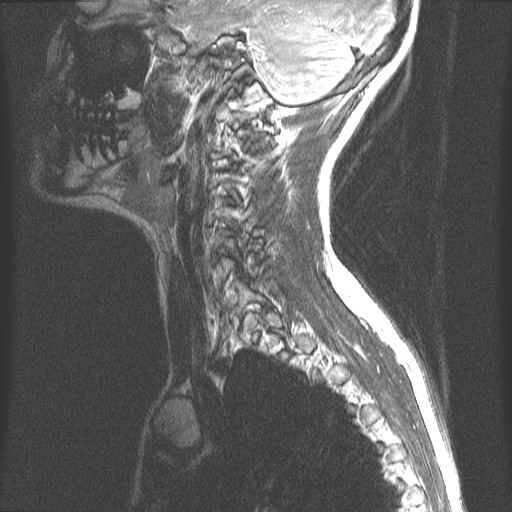

Centrale Wervel Zuil